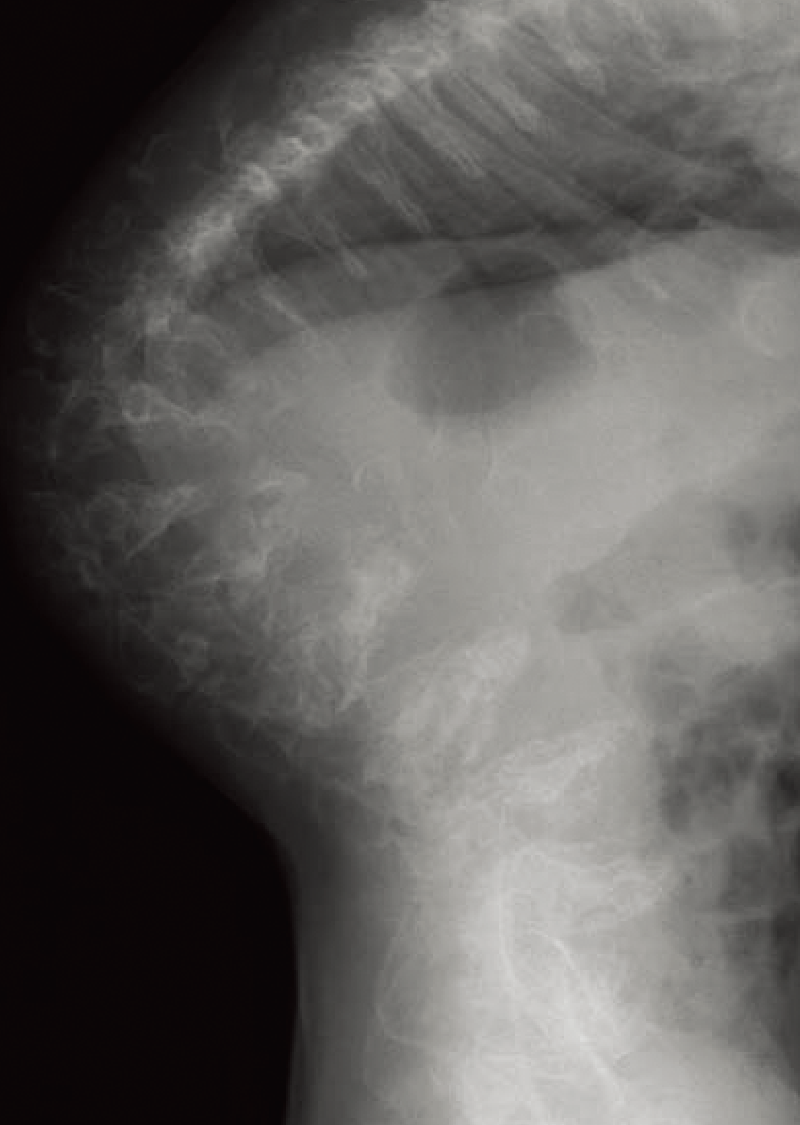

四肢長管骨では骨幹端部の広がり(metaphyseal flaring)がみられ、関節は腫大する(B)。

B. 両下肢正面像(5歳、男):骨幹端部の広がり(metaphyseal flaring)と関節腫大を認める。